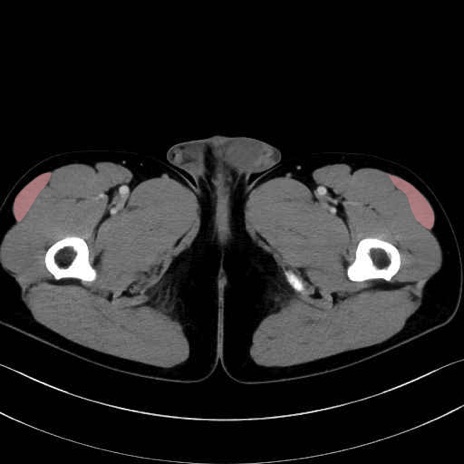

大腿筋膜張筋 (Tensor fasciae latae)